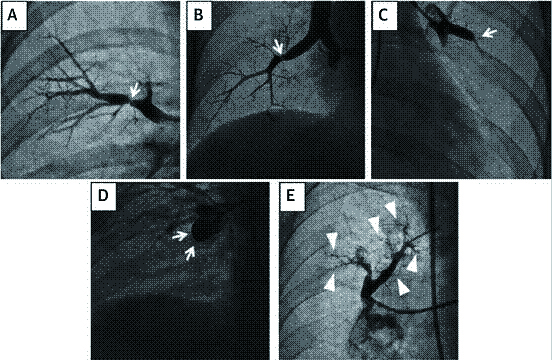

根肺动脉造影的影像学变现的患者病变部位的受损程度及远端血流情况,以新的形态学标准分为以下五类:A型,环状狭窄;B型,网状病变;C型,次全病变;D型,完全闭塞;E型,弯曲病变[40] (图 4)。